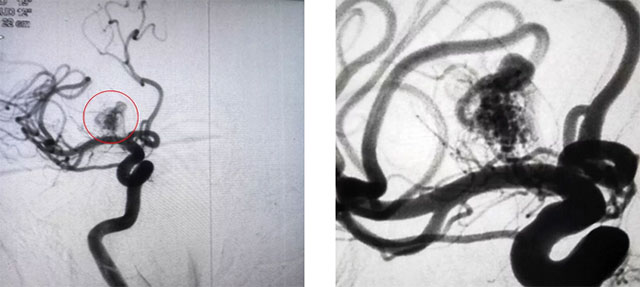

▲ 患者脑动静脉畸形DSA显像图(栓塞前后)

患者两周前突发头痛,脑血管CTA:右侧前颅底语气团簇状血管影。经医院DSA检查,确诊为功能区动静脉畸形。其供血动脉来源是大脑前动脉的分支血管Heubner回返动脉(功能血管),该血管与肢体活动密切相关。该动静脉畸形位于功能区,引流静脉中有部分导入深部静脉,畸形团大小3cm*4cm,根据Spetzler&Martin分级,综合评分3分,属于级别较高的畸形。

再次造影发现畸形团大部分不显影,手术顺利,随后予以撤除导管后封堵局部穿刺点。术后,患者遵嘱动作,无四肢无活动及感觉障碍,无神经功能缺损,手术取得成功。本次栓塞60%以上,后期出血风险相对较小,下一步可结合伽马刀治疗。